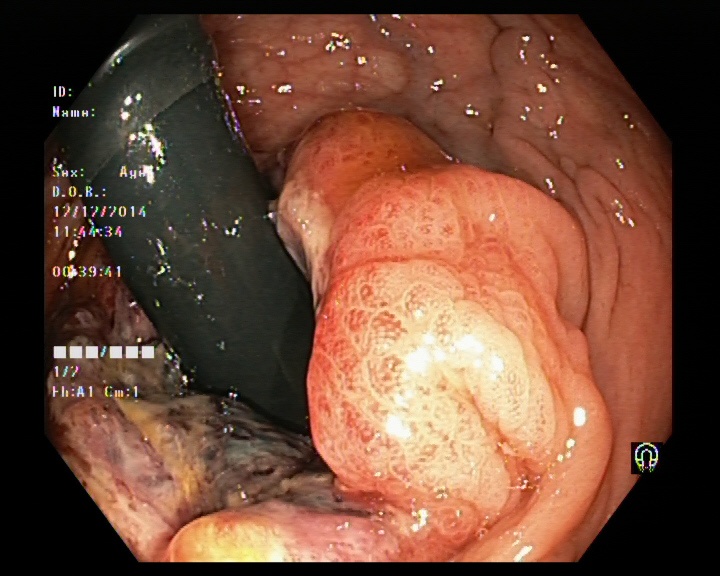

The Kvaris-SEG (Jha et al., 2020c) training dataset can be downloaded from https://datasets.simula.no/kvasir-seg/. It contains 1,000 polyp images and their corresponding ground truth mask as shown in Figure 1. The dataset was collected from real routine clinical examinations at Bærum Hospital in Norway by expert gastroenterologists. The resolution of images varies from to pixels. Some of the images contain a green thumbnail in the lower-left corner of the images showing the scope position marking from the ScopeGuide (Olympus) (see Figure 2). We annotate another separate dataset consisting of 160 new polyp images and use the resulting dataset as the test set to benchmark the participants’ approaches. Figure 2 shows some examples of test images used in the challenge.